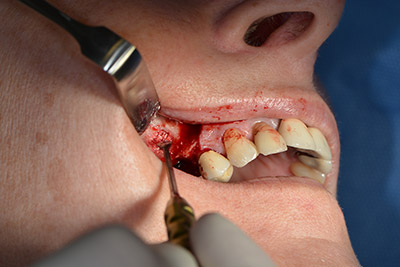

El guiado clásico del corte (crestal, descarga bucal) y la preparación del colgajo mucoperióstico permiten obtener una buena visión global.

En este caso se utilizan implantes Sky (Bredent), cuyo protocolo quirúrgico exige el fresado piloto a unas 1.200 rpm (figura 9).